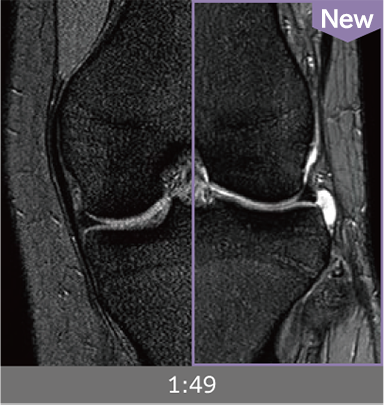

Combining high-speed imaging technology with Advanced Reconstruction enables shorter exams and reduces image noise.

Images can be obtained at high speed by combining two technologies: IP-RAPID, which reduces imaging time while maintaining image quality, and Advanced Reconstruction to improve image quality.

Under-sampling reduces imaging time, and iterative reconstruction with IP-RAPID reduces noise and artifacts.

In addition, Advanced Reconstruction further eliminates noise and produces images that are easier to use in making a diagnosis.